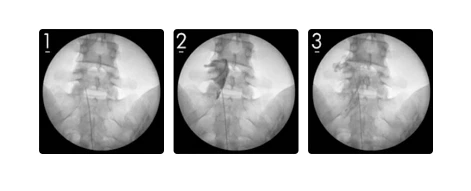

통증을 감소시키고 수면 장애를 완화하기 위한 약물치료에는 진통제, 항우울제, 항경련제, 근이완제로 개발된 약제를 사용합니다. 에이스병원에서는 실시간 영상 촬영 하에 얇은 카테터를 삽입하여 목, 허리의 통증 유발 부위에 정확하게 도달한 후 미세유착을 박리하고 통증을 없애는 간단하고 효과적인 시술방법인 경막외강감압 신경성형술로 섬유근육통 환자들의 통증을 완화시켜주고 있어요.

신경성형술.PNG